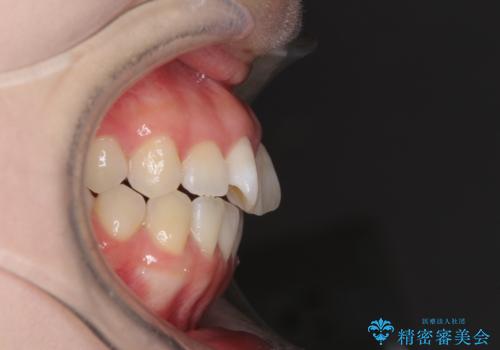

- 前歯の捻れと、ちょっとした出っ張りを気にして来院された患者様です。

歯と歯の間を削る(IPR)ことでデコボコを解消し、インビザラインで整えることとしました。

インビザライン治療特有の奥歯が接触しない時期が続き、当初予定よりも期間がかかりましたが、最終的には安定した咬み合わせと、整った前歯になりました。